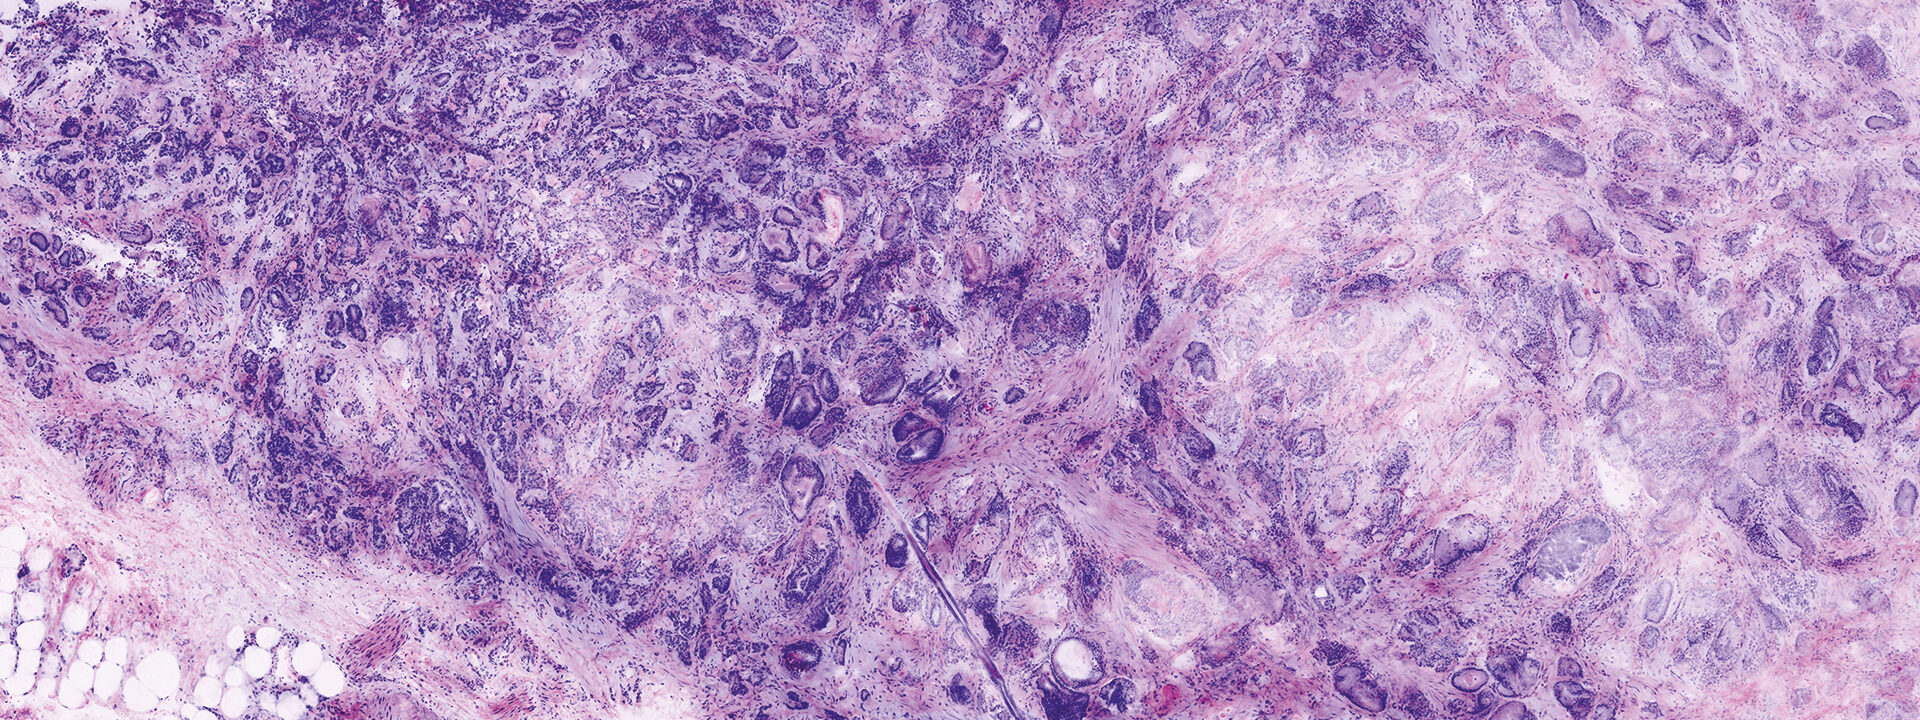

Images courtesy of Dr Javiera Pérez-Anker.

Basal cell carcinoma; imaged with the VivaScope 2500 (left) and after H&E staining (right)